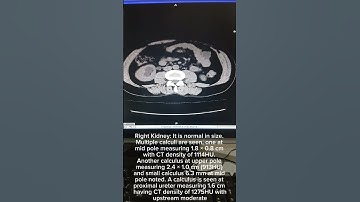

How to make 3D cutting KUB manually in CT Scan Urography |#radioimaging #ctscan #radiology